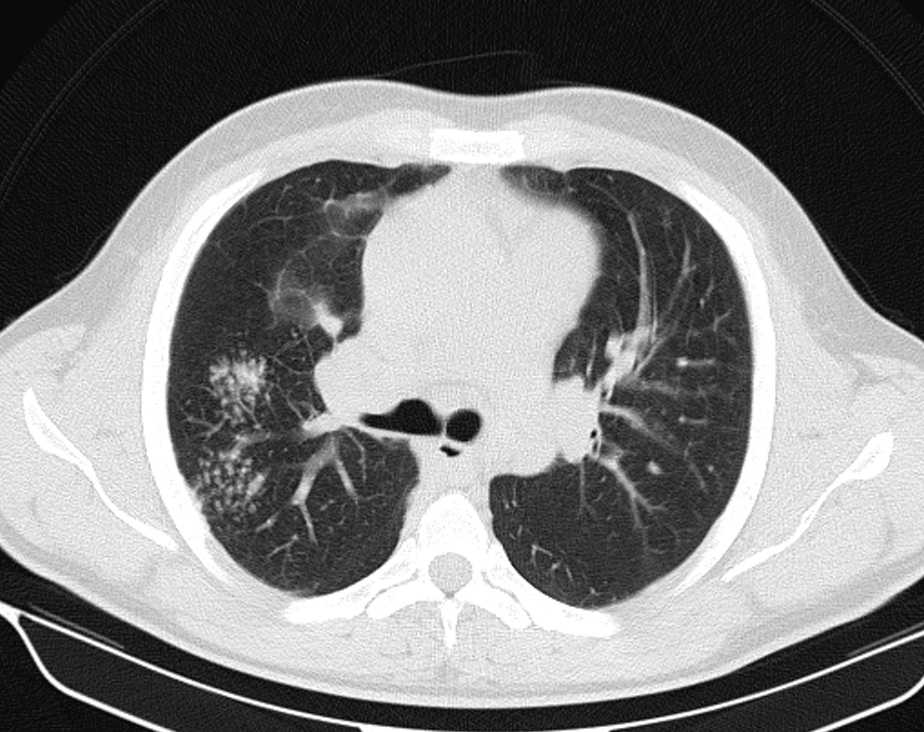

Фотографии и снимки КТ легких без контрастных веществ

Раздел: Визуальный дайджест